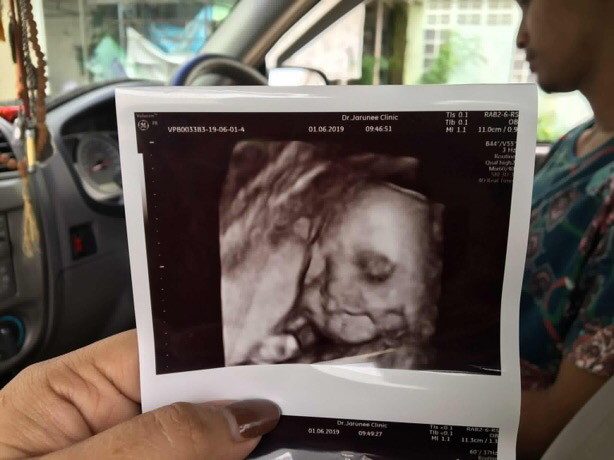

ซาวตอน. 23weekค่ะ